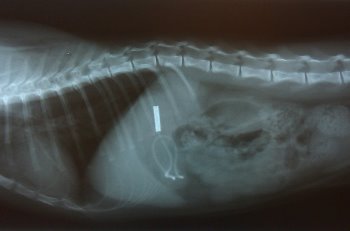

X-ray of a cat that ate a girl's hair tie